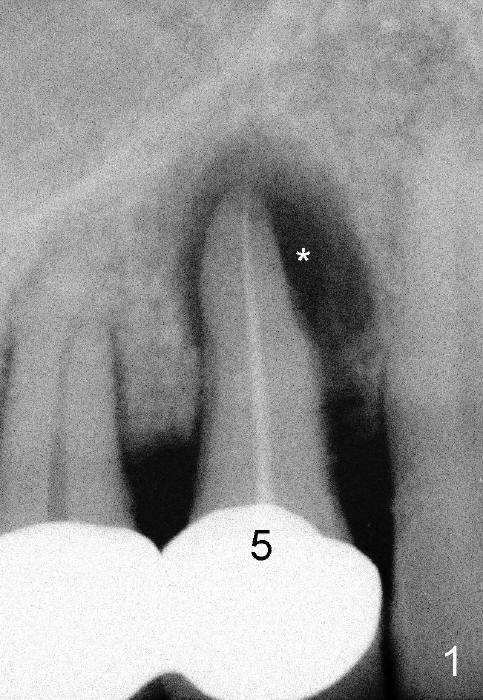

A 57-year-old man refuses treatment for the tooth #5 for 22 months (Fig.1). He suddenly shows up because of severe bleeding from the fistula of the tooth (Fig.2 <). After lengthened discussion, he agrees extraction (Fig.4) and immediate implant (Fig.5-8).

In spite of large periapical radiolucency (Fig.1 *), osteotomy is easier than expected. Use 2 mm pilot drill, 2.5-3.5 mm reamers from 14 mm (bottom of the socket) to 17 mm (sinus floor). The initial point for osteotomy at the bottom of the socket is easy to establish, because it is flat. By the time 5x20 mm tap is inserted, it is palatal (Fig.5). It is mandatory because the buccal plate has been perforated. The tap has to be inserted deeper (from 17 mm to 20 mm, Fig.6) to achieve stability. Insertion torque of 5x20 mm implant (Fig.7 I) is > 60 Ncm. The implant remains palatal so that there is space for bone graft (Fig.8 *). But the bone graft is a little over packed; there is no room to place collagen dressing. The latter will be dislodged and bone graft will be lost if perio dressing is loose prematurely. The perio dressing may have to be re-applied. Depth of bone graft is deemed sufficient if the implant threads are covered. Maximum will be on the rough surface. Physiologically, bone does not extend to the gingival margin.